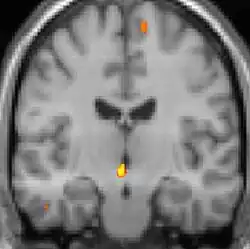

Tomografia PET mostrando áreas ativadas na dor.

As reais causas da cefaleia em salvas (CES) ainda são desconhecidas, mas, de acordo com alguns estudos, os padrões das crises, as influências pelo horário do dia e as estações sugerem que o relógio biológico do corpo está envolvido. Nos seres humanos, o relógio biológico está situado no hipotálamo. Durante um ataque, o hipotálamo libera substâncias químicas que podem estimular as células nervosas no cérebro, causando dor e outros sintomas. A hiperatividade nervosa também pode causar um alargamento (vasodilatação) das artérias no lado afetado do cérebro. Uma teoria é que as dores são causadas por um alargamento dos vasos sanguíneos, que pressionam sobre os tecidos nervosos próximos, causando dor.[5] Exames de ressonância magnética sugerem dilatação da artéria oftálmica durante uma crise de cefaleia, enquanto a tomografia por emissão de pósitrons (PET) revela atividade dentro do seio cavernoso. Em alguns casos, existem fatores genéticos também, pois é mais comum entre familiares.[6]